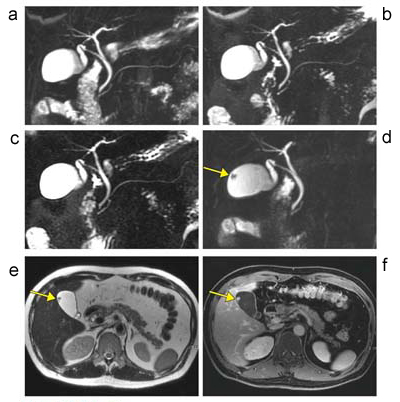

図3 直腸がん肝転移

a:呼吸同期脂肪抑制FSE法T2強調画像 / b:呼吸同期 DWI (b値800) /

c:Gd-EOB-DTPA造影ダイナミック動脈早期相

(撮像時間double phase 12秒×2=24秒)

d:Gd-EOB-DTPA 門脈早期相 /

e:肝細胞相横断像 /

f:肝細胞相冠状断像

*c〜fはすべてLAVA-FLEX Water image

B1不均一性による画像信号ムラはないが,32chコイルを使用しているため,コイル近傍の信号がやや高く見える。T2強調画像(a),DWI(b)では,肝内の多発転移巣(→)は高信号を示す。転移巣は,造影ダイナミック動脈早期相(c)でリング状に染まり,肝細胞相(e,f)では明瞭な低信号を示す。